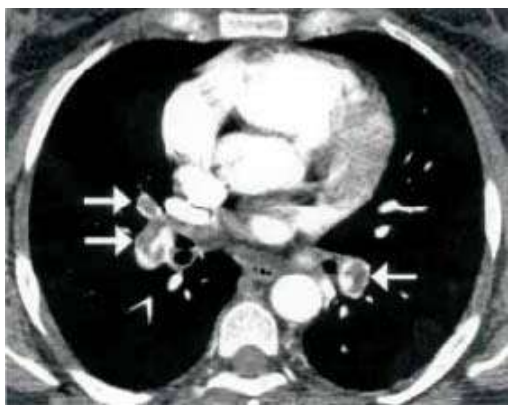

......Uma paciente de 45 anos de idade, que nega comorbidades, exceto obesidade, relata ter realizado cirurgia ortopédica, há dois meses, por uma queda da própria altura. Apresenta quadro de dispneia súbita, iniciada há cerca de 4 h. Ao exame, PA de 120 x 80 mmHg, FC de 102 bpm, FR de 24 irpm e sat. de o2 de 96% em ar ambiente. Nos exames admissionais, troponina 0,003 (VR 0,004), Ur 0,6, Cr 1, Hb 12,5, leucócitos 8.000 e plaquetas 180.000. Ecocardiograma transtorácico: fração de ejeção de 65% em átrio esquerdo 32; função sistólica do ventrículo esquerdo e do ventrículo direito preservadas; TAPSE 25; e PSAP 28. Realizou uma angiotomografia, que identificou a imagem seguinte.

J Bras Pneumol 2004; 30(5) 474-9

Com base nesse caso hipotético, assinale a alternativa que apresenta a conduta mais adequada.